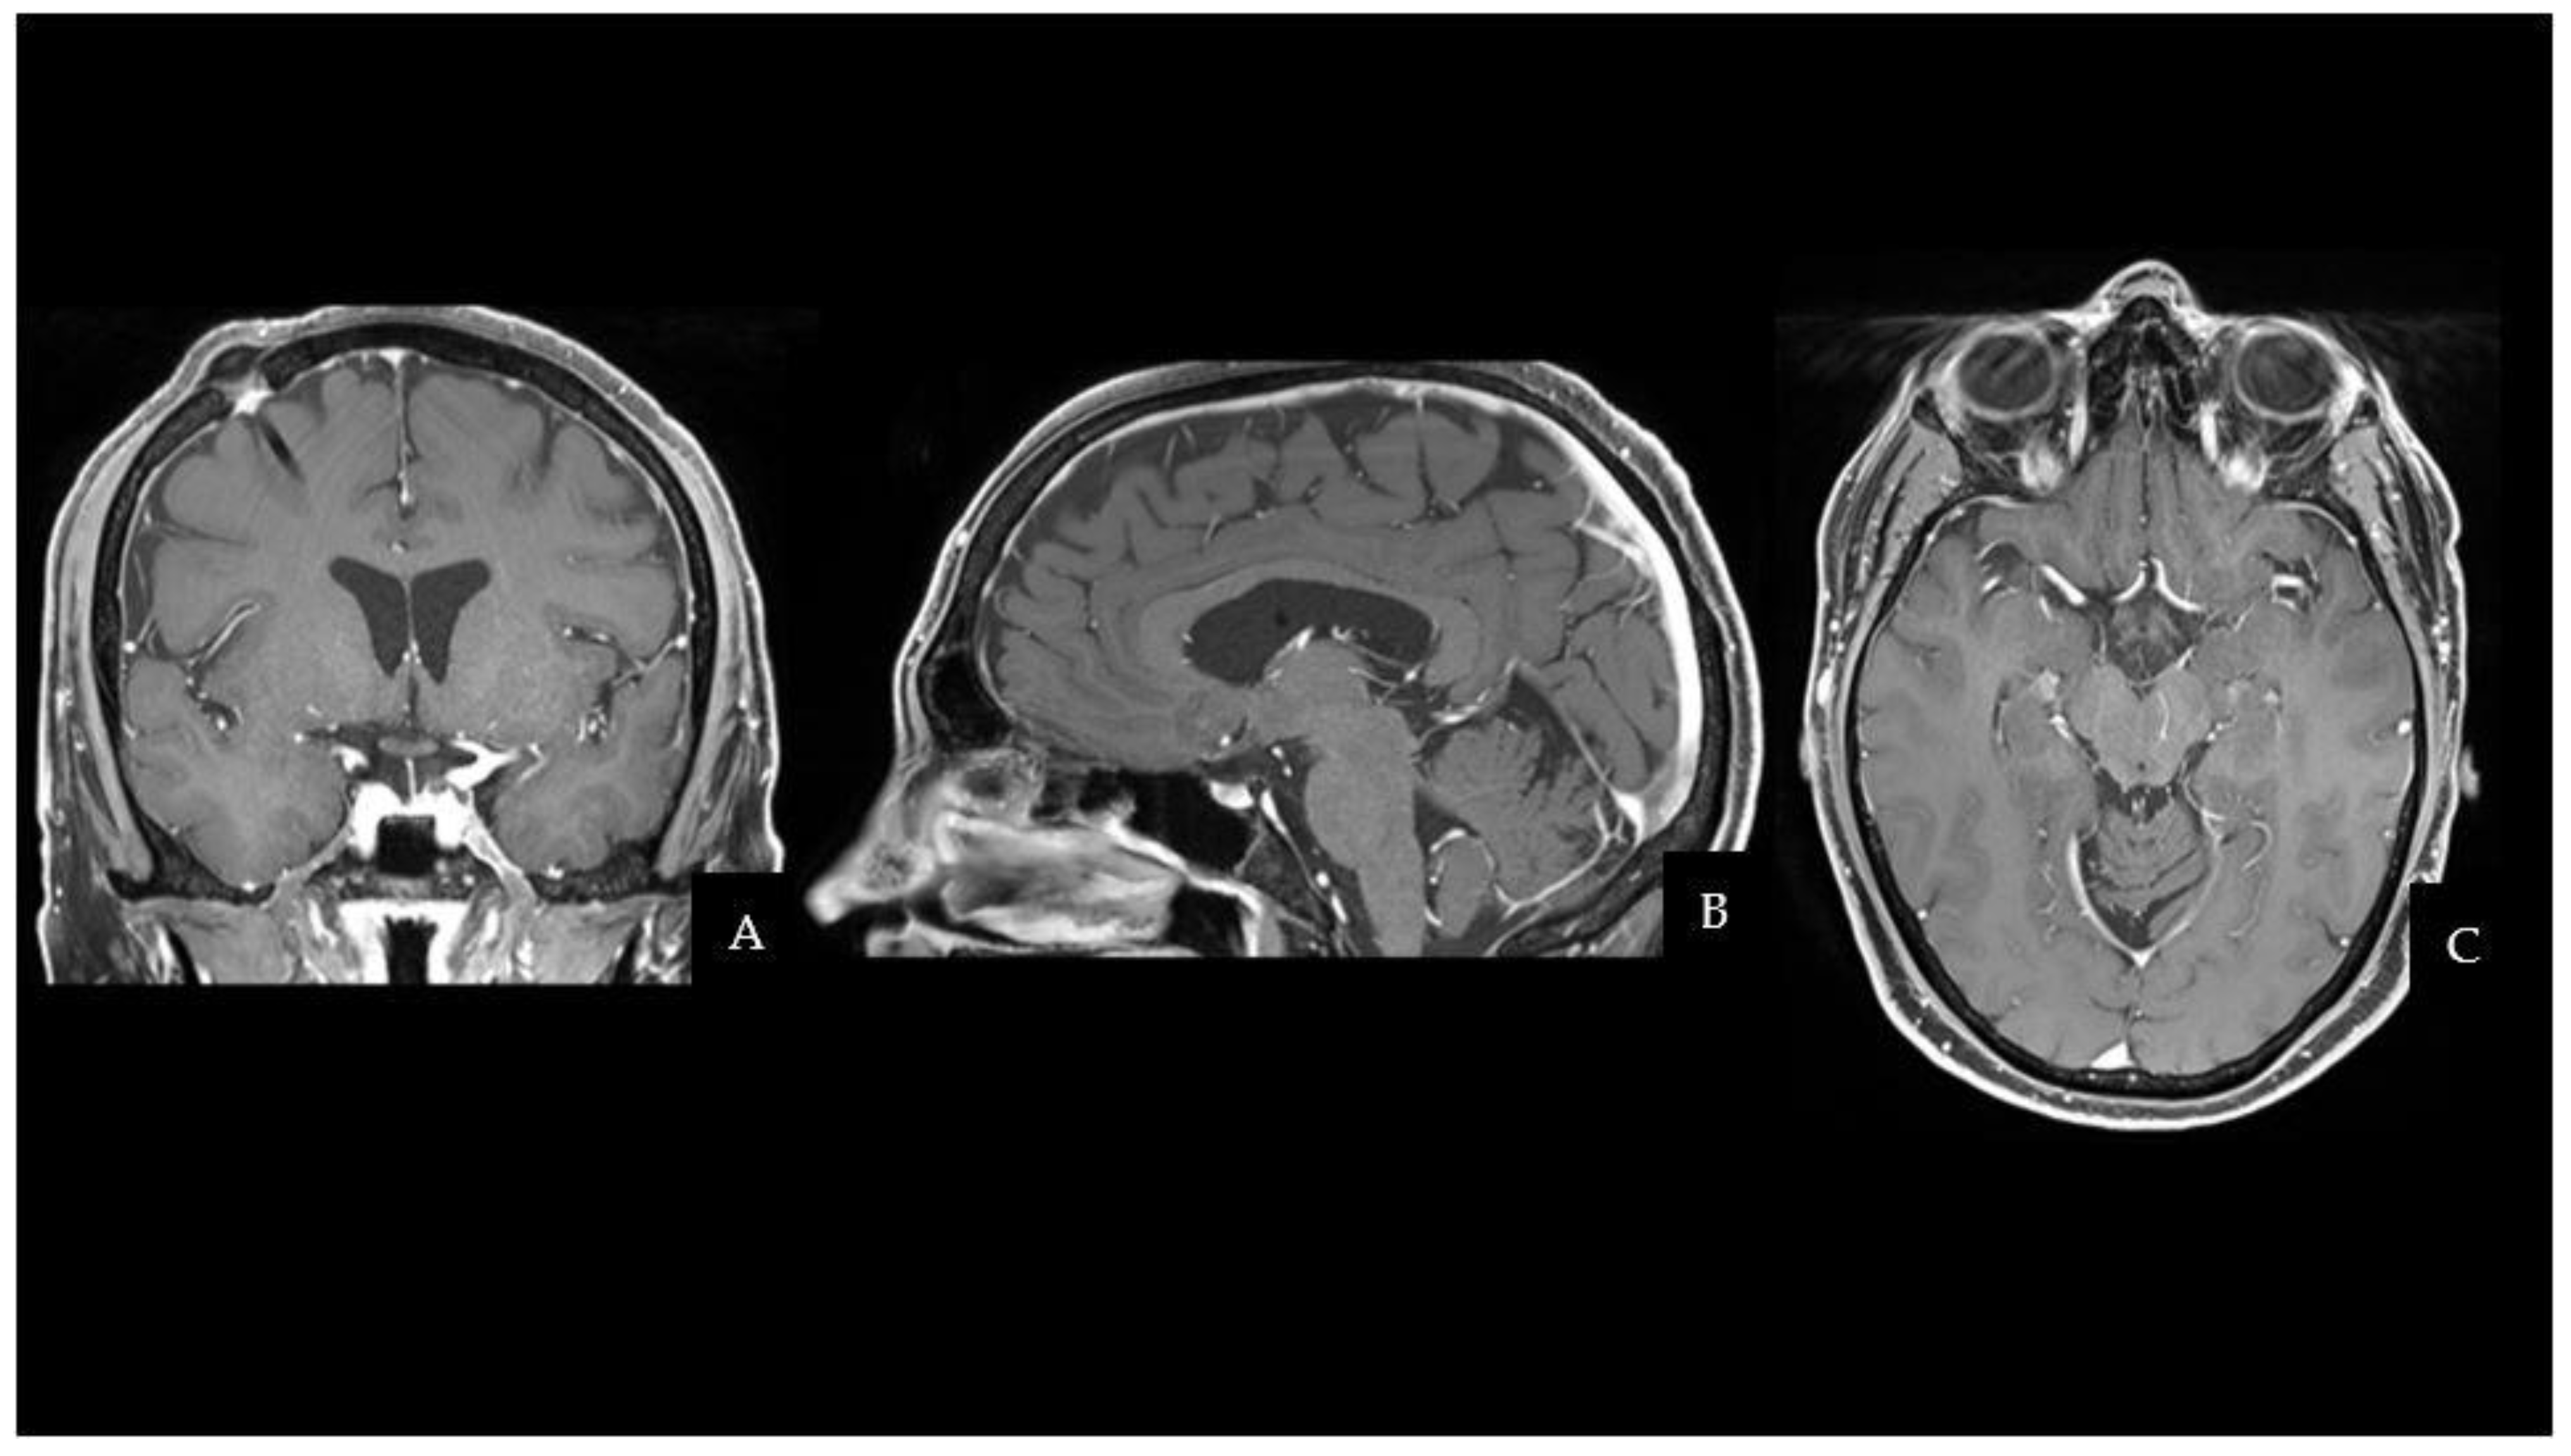

The CT scan was followed by a cerebral magnetic resonance imaging (MRI) scan that showed a pseudonodular suprasellar lesion, isointense with grey matter on both T1- and T2-weighted images, with heterogeneous enhancement after contrast administration. The lesion extended from the pituitary peduncle to the hypothalamic region and the optic tracts, with a maximum craniocaudal extension of 3 cm.

Taking into account the patient past medical history of testicular GCT, neuroradiological findings were considered compatible with a CNS GCT (Figure 1). However, pituitary adenoma, craniopharyngioma, metastases, sellar region lymphoma and meningioma had to be ruled out. Hence, a neurosurgical hospitalization for further diagnostic investigations was indicated.

Figure 1. CE-T1Weighted MRI scan showing a pseudonodular suprasellar lesion extended from the pituitary peduncle to the bilateral hypothalamic region, with a maximum craniocaudal extension of 3 cm (the lesion is highlighted by red arrows). (A) Coronal sequence. (B) Sagittal sequence. (C) Axial sequence. Abbreviations: contrast-enhanced T1Weighted (CE-T1W); magnetic resonance imaging (MRI).